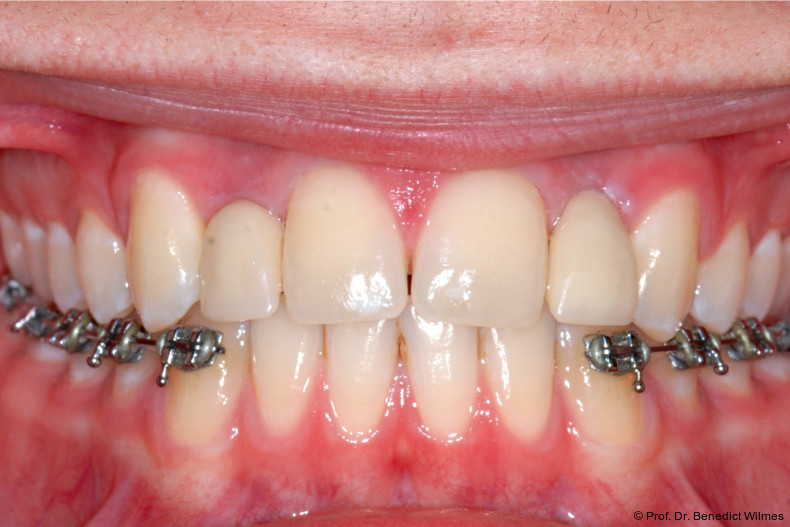

Ein 14-jähriger Patient wurde bei Aplasie der beiden oberen seitlichen Schneidezähne mit dem Ziel der beidseitigen Lückenöffnung kieferorthopädisch therapiert (Abb. 1a+b). Zum Ende der kieferorthopädischen Behandlung wurden zwei Miniimplantate in Regio 2er als temporärer Zahnersatz inseriert (Benefit System, PSM, 2 x 13 mm, Abb. 2a+b). Nach Abdrucknahme wurden Kronen auf den Peek-Abutments modelliert und diese mit Kunststoff auf die Abutments geklebt (Abb. 3a–d). In den Abbildungen 3 und 4 sind die klinischen und röntgenologischen Nachkontrollen innerhalb der nächsten achteinhalb Jahre dokumentiert. Man erkennt einen sowohl in der Höhe als auch in bukkopalatinalen Breite verbleibenden gesunden Knochen ohne Anzeichen einer Atrophie. Im Alter von 23 Jahren wurden die definitiven Implantate ohne die Notwendigkeit einer Augmentation eingesetzt (Abb. 5) und nach Einheilung prothetisch versorgt (Abb. 6a–e und Abb. 7a–c).

Bei einer elfjährigen Patientin fehlten bei Zustand nach Frontzahntrauma im Alter von neun Jahren beide oberen mittleren Schneidezähne (Abb. 8a+b). Als temporärer Ersatz wurden Miniimplantate (Abb. 9, 2 x 13 mm) eingesetzt und Kronen im Labor angefertigt, welche auf den Miniimplantaten verschraubt wurden (Abb. 10a+b). Die Miniimplantate wurden im Alter von 19 Jahren, also nach achtjähriger Nutzung (Abb. 11a+b), durch dentale Implantate ersetzt.

Nach Abschluss der kieferorthopädischen Pfeilerverteilung wurden zwei Miniimplantate in Regio 3er inseriert (2 x 13 mm). Nach Herstellung im Labor wurden Kronen auf den Miniimplantaten aufgeschraubt (Abb. 13+16a–d). Auch hier wurde darauf geachtet, dass die Kronen aus der Okklusion geschliffen wurden (Abb. 14). Bei den Nachkontrollen zeigten sich ebenfalls stabile Miniimplantate und ein entzündungsfreies Implantatlager ohne erkennbare Atrophie des Knochens (Abb. 15 und 16a–d).